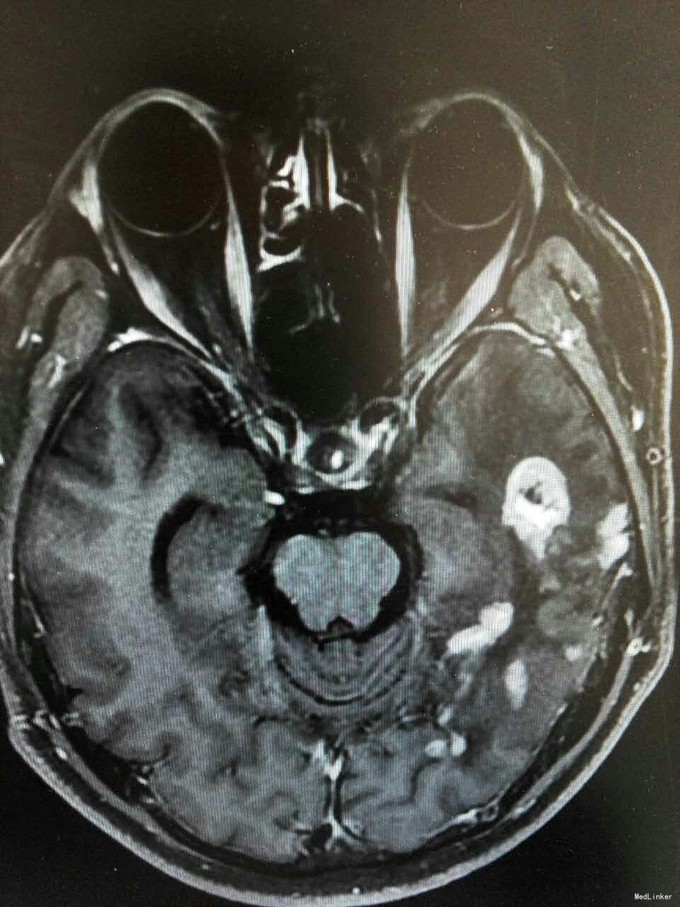

患者姜磊,男,49岁,主因"发作性视野缺损、失认8年余"于2015-11-20再次入我院,患者缘于8年前无诱因出现发作性视野缺损,伴阅读能力、理解力、认知能力下降,每次发作症状持续约3-5分钟左右,可自行缓解,无意识丧失、视物旋转、言语不利,无肢体活动障碍、大小便失禁。入院复查头颅MRI平扫+增强示:原左侧小脑幕、颞叶炎症治疗后,与2014-09-10日片比,病灶较前增多、增大。8年来间断在我院以:颅内非特异性炎症、症状性癫痫、高血压病 住院治疗,患者症状时轻时重,病灶反反复复,激素治疗有效。 病史汇报: 于2007年12月12日因"发作性视野缺损、失认1月"入我院,查头颅MRI示:左侧幕上颞底片状异常信号,并局部强化,考虑:炎症可能,肿瘤不排除;行腰穿检查,颅压120mmH2O ,外观清亮,脑脊液常规、生化均正常。脑电图轻度异常。给予复方磺胺甲恶唑片、青霉素、阿昔洛韦、激素(醋酸泼尼松片)等治疗。 2008年1月8日复查头颅MRI示:原左侧幕上颞底炎性病变范围缩小,综合考虑原颅内病变为炎性病变。于2008年1月19日出院,共住院37天。出院后仍间断出现发作性视野缺损症状。于2008-5-6复查头颅MRI示原左颞叶病变范围有缩小,支持局灶性脑炎的诊断。于2008.5.22~6.12予青霉素480万单位2/日巩固治疗30天。鉴于反复出现发作性视野缺损症状,于2008.6.5诊断性服用卡马西平片后上述症状未再发作,于是坚持服用卡马西平片(0.1g3/日)1年,服药期间未再出现发作性视野缺损症状。 于2012-05-29再次因"发作性双眼右侧视野缺失、闪烁感6天"入院,查头颅MRI示:原左侧幕上颞叶病变治疗后改变,考虑为炎性病变,结核可能。行腰穿示压力125mmH2O,脑脊液常规:颜色:无色,透明度:水样透明,潘氏试验:阴性,红细胞计数:80×106/L,白细胞计数:0x106/L,单个核细胞75%,多核细胞20%,脑脊液生化:蛋白508mg/L,葡萄糖3.3mmol/L,氯化物115.4mmol/L。脑电图印象:基本节律为低-中幅的α波, 频率调幅调节欠佳,分布可,左侧枕区波幅可见较右侧枕区减低。头前区可见少量低幅θ波及β波。深呼吸中见4-5hz慢波增多,有时呈短至中程节律,头前区为著,左侧偏胜。深呼吸后恢复好。睁闭眼试验:半抑制。闪光刺激:未见异常。脑电地形图:以α功率为主,可见θ功率。结论:轻度弥慢性异常脑电图及地形图;给予改善循环、营养神经、活血化瘀、脱水、激素等对症治疗。住院期间未再出现上述发作。 于2013-1-5再次因"发作性双眼右侧视野缺失、闪烁感1周。"入院,行头颅MRI示:左侧颞叶病变治疗后改变,与2012-07-24日片比,左侧小脑幕病变较前增大,左侧颞叶出现新病灶。给予改善循环、营养神经、活血化瘀、抗癫痫、抗感染(青霉素)、激素冲击(甲强龙)治疗后病情好转,于2013-4-15复查头颅MRI病灶再次缩小。患者出院后上述症状仍偶有发作。 于2014-5-12、2014-9-10复查头颅MRI病灶有增大趋势,再次给予抗炎(激素)等对症治疗后,于2014-11-24再次复查头颅MRI示:原左侧小脑幕、颞叶病变治疗后改变,与2014-09-10日片比较,较前明显缩小,水肿较前明显减轻。